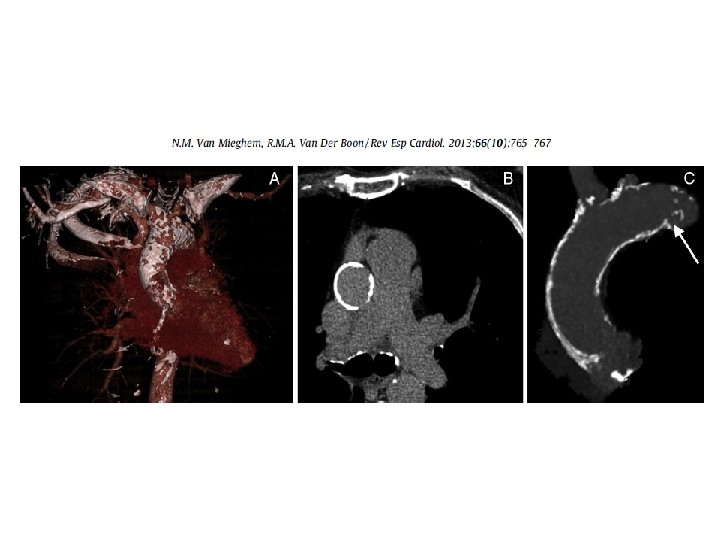

Figure 3 Cardiopulmonary Bypass Management and Neurologic Outcomes: An Evidence. Based Appraisal of Current Practices Hogue, Charles W. Jr; Palin, Christopher A. ; Arrowsmith, Joseph E. Anesthesia & Analgesia. 103(1): 21 -37, July 2006. doi: 10. 1213/01. ANE. 0000220035. 82989. 79 Figure 3. Epiaortic ultrasound images and pathologic specimen depicting atherosclerosis of the ascending aorta. Transverse (panel A) and longitudinal (panel C) ultrasound scans demonstrate circumferential intimal thickening particularly anteriorly (arrows). Pathologic specimen (panel B) confirms the diagnosis. Transverse (panel D) and longitudinal (panel F) images from a second patient demonstrate intimal thickening (small arrows) and large sessile atheroma confirmed with the pathologic specimen (panel E). The pathologic specimens were made available when the patients underwent replacement of the ascending aorta. Reprinted with permission from Dávila-Román et al. (73). Copyright © 2015 International Anesthesia Research Society. Published by Lippincott Williams & Wilkins. 19